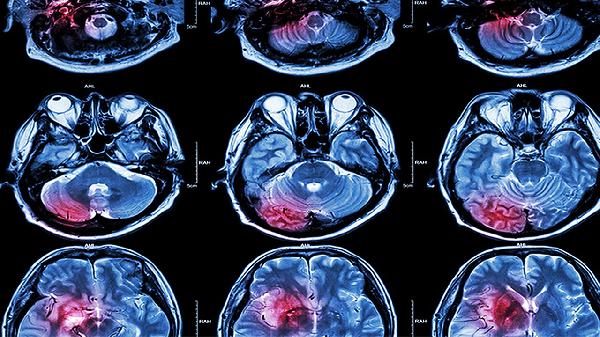

2、脑栓塞

对心源性栓塞如房颤引起的脑部血管堵塞有一定辅助疗效。患者多存在心律不齐病史,症状突发且较重。使用时需明确栓塞来源,配合华法林钠片等抗凝治疗。心脏瓣膜病引起的栓塞需优先处理原发病。

3、短暂性脑缺血发作

适用于反复发作的短暂性神经功能缺损,如一过性黑蒙、肢体无力等。该病是脑梗死的前兆状态,脑血栓片可帮助改善脑供血。需同时控制血压血糖,必要时联合盐酸氟桂利嗪胶囊预防发作。